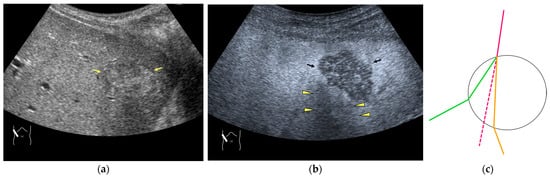

Current US machines reconstruct B-mode US images based on the assumption that sound passes through all parts of human tissues in a straight line and at a constant acoustic velocity (1540 m/s), and this assumption is applied to all scanning planes. The displayed position in a US image usually corresponds with the actual position on the structure. Strictly speaking, however, the acoustic velocity changes according to the tissues [44,45]. Thus, when a plane containing tissues with different acoustic velocities is scanned, sound refraction occurs at the interface between these tissues according to Snell’s law. As a result, the displayed position of point A (the true location) along the line that passes through the interface is falsely displayed at point A’ (a different position) in the B-mode US image as if there was no sound refraction. This refraction artifact is clearly seen in a cirrhotic liver (Figure 3), around a round mass (e.g., a hepatic cyst) (Figure 4) and below the rectus muscles in the transverse scanning plane of the upper abdomen (Figure 5). We will now provide a brief explanation for these three artifacts (Figure 3, Figure 4 and Figure 5). In macronodular liver cirrhosis, sound refraction occurs at the irregular hepatic surface, resulting in the improper positioning and display of echo brightness in the US image [44,45,46], giving the appearance of a “tricolor flag” [46] (Figure 3). When a US beam passes through a mass with an acoustic velocity different from that of the surrounding hepatic parenchyma, it changes direction twice due to sound refraction, first at the liver parenchyma–mass lesion entrance interface and again at the mass lesion–liver parenchyma exit interface. The liver structure behind the mass lesion thus appears to be deformed in B-mode US and heterogeneous in CEUS (Figure 4). As has been reported, sound refraction occurs most clearly at both edges of a mass lesion, and the degree of sound refraction is nearly proportional to the incidental angle of the US beam striking the liver parenchyma–mass lesion interface. Globally speaking, the degree of sound refraction is accentuated as the US beam strikes peripheral to the mass lesion. This is why the posterior echo behind the mass lesion is not homogeneous, as observed in Figure 4. In the transverse scanning of the upper abdomen, the US beam is largely refracted, first at the anterior wall of the rectus muscles and then at the posterior wall of the muscle (Figure 5c). As a result, the liver below the rectus muscles is more or less deformed in B-mode US and CEUS, as seen in Figure 5a,b. The most useful prevention strategy is to use the reference B-mode image (the so-called dual-image technique), which allows for a simultaneous comparison between the CEUS and B-mode images.

Figure 4.

Refraction artifact (2): heterogeneous enhancement behind a mass lesion (liver metastasis). (a) Gray-scale US shows a 5 × 4 cm liver mass (arrows) in the right lobe. (b) CEUS shows it to be enhanced (black arrows, mass lesion). The liver parenchyma behind it is also coarsely enhanced (arrowheads). (c) A schematic drawing of sound refraction through a round mass (black circle) shows that the US beam is refracted twice at the liver parenchyma–mass lesion interface. Non-refractive lines are marked with solid and dashed pink lines. When the acoustic velocity in the mass is less than that in surrounding tissue, it is indicated with an orange line. When it is greater than that in surrounding tissue, it is indicated with a green line.

Figure 5.

Refraction artifact (3): hypoenhanced lines due to US refraction. (a) CEUS shows many hypoechoic lines throughout the liver parenchyma via transverse scanning (arrowheads). (b) The liver’s left lobe shows none of the lines seen in (a) via sagittal scanning. (c) A schematic drawing of sound refraction due to rectus abdominus via transverse scanning plane. The US beam changes direction twice, first at the surrounding tissue–rectus muscle interface, then at the rectus muscle–surrounding tissue interface.